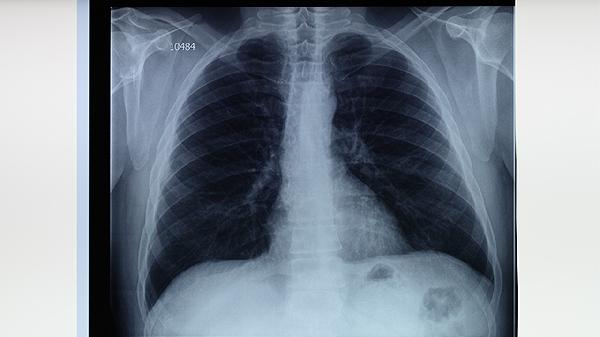

肺結(jié)核患者可通過(guò)適量食用高蛋白食物、富含維生素食物、滋陰潤(rùn)肺食物、補(bǔ)氣養(yǎng)血食物及易消化食物輔助治療。肺結(jié)核是由結(jié)核分枝桿菌感染引起的慢性傳染病,食療需結(jié)合規(guī)范抗結(jié)核藥物治療。